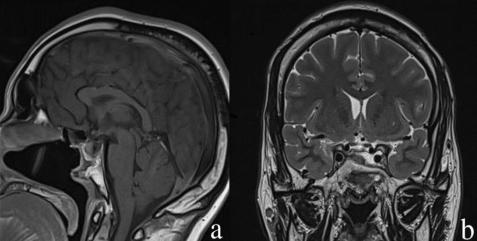

Considering these findings, an endonasal endoscopic repair of the defect was planned and achieved for him. Using a binostril approach, we have raised a nasoseptal flap on the right side with preservation of the olfactory mucosa. after performing a sphenoidotomy, a significant amount of CSF was aspirated and the defect was identified. The repair was completed first by a small amount of fat graft, and then a generous covering using a vascularized flap was used. the nose was packed at the end of the procedure. The postoperative course was uneventful and the patient was discharged 3 days after with antibiotic treatment. he was seen 10 days after in the office for packing removal. Follow-up at two years after surgery revealed a significant reduction of the tumor size and normalization of the Prolactine levels with a good vascularized flap at the imaging analysis (figure2).

Figure 2: a- sagittal T1 with contrast showing the vascularized nasoseptal flap without CSF collection in the sinus. b- coronal T2 MRI showing a good response for medical treatment with tumor shrinkage.